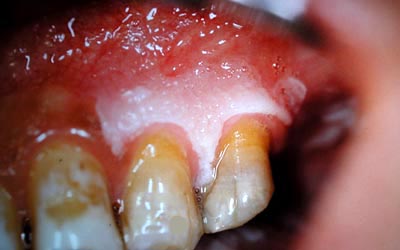

LA LEUCOPLASIE BUCCALE

La leucoplasie fait partie des kératoses buccales. Ce qui signifie que cette lésion apparaissant sous forme de taches blanches est constituée d’une kératinisation de l’épithélium. Selon le Dictionnaire de Médecine Flammarion, la « kératinisation est un processus complexe au cours duquel les cellules de l’épiderme issues des cellules de la couche basale ou kératinocytes, deviennent au terme de profondes transformations, des cellules cornées superficielles, anucléées et riches en kératine ». Selon M. DECHAUME, la leucoplasie est une lésion double, portant sur l’épithélium mais également sur le chorion sous-jacent. Au niveau de ce dernier, il existe une infiltration variable de cellules rondes autour des vaisseaux, parfois des lésions d’endo-périvascularite et de sclérose conjonctive. A l’évidence pour les homéopathes, l’endo-périvascularite évoque le mode réactionnel luétique. Par ailleurs, DECHAUME affirme que lorsque la leucoplasie résulte d’irritations externes, c’est la couche superficielle de l’épithélium qui se kératinise, alors que la leucoplasie syphilitique débute dans le chorion.

L’étiologie de la leucoplasie valorise certains causes locales: tabac surtout, ensuite les irritations provoquées par des dents cariées avec arêtes vives, l’électrogalvanisme buccal favorisé par la présence de plusieurs métaux, puis l’abus d’alcool ou d’épices. Parmi les causes générales, seule la syphilis est citée. Dans le Manuel MERCK, la leucoplasie est citée dans le chapitre des cancers buccaux, mais contrairement à une idée répandue, la leucoplasie n’est pas une lésion précancéreuse fréquente puisqu’elle ne concernerait que moins de 5% des cas.

La leucoplasie concerne surtout les hommes entre 30 et 50 ans. La localisation la plus fréquente est la région rétrocommissurale sur la face interne des joues (leucoplasie labiale des fumeurs décrite par Lortat-Jacob). Puis la langue arrive en deuxième position: moitié antérieure, face dorsale.

Plusieurs formes cliniques sont décrites: la leucokératose encore appelée leucoplasie verruqueuse, qui selon DECHAUME serait le prélude habituel à la cancérisation - l’ulcère leucoplasique s’aggraverait également par cancérisation.